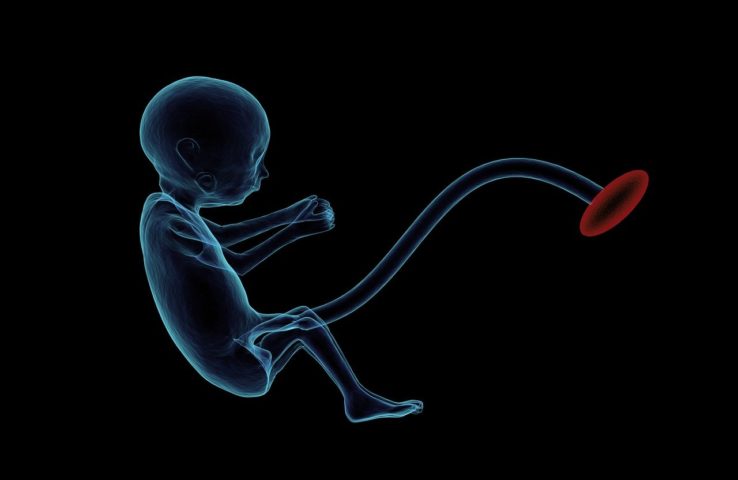

Litopédio se caracteriza pelo óbito de um feto durante a gravidez, seguido pela calcificação dele dentro do abdômen da mulher. Foto: reprodução -

Na época, especialistas disseram que essa condição, embora seja muito rara, pode acontecer quando o feto acaba se desenvolvendo fora do útero. Foto: Raman Oza por Pixabay -

â??Normalmente a mulher não apresenta sintomas, por isso essa condição acaba sendo diagnosticada por acaso somente anos depois da gravidezâ?, disse a obstetriz. Foto: reprodução